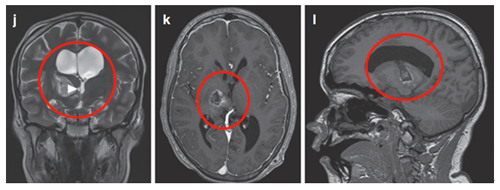

病例四:10岁男孩C1-C3脊索瘤

10岁患儿临床表现为头晕颈痛、复发性咽喉感染和吞咽困难,确诊C1-C3脊索瘤伴上呼吸道压迫。经详细评估后,行经口、经腭、经下颌入路次全切除术。

术后影像显示C2-C3神经孔残留病变,遂制定个性化放疗方案。患儿对70Gy光子放疗反应良好,耐受性佳,残留病变明显缩小且无显著放疗副作用。

据文献报道(1973-2014年808例原发性脊索瘤数据),脊索瘤5年生存率达68.4%,10年生存率为39.2%。该病例随访10年无复发,未出现神经功能缺陷,验证了综合治疗方案的长期有效性。